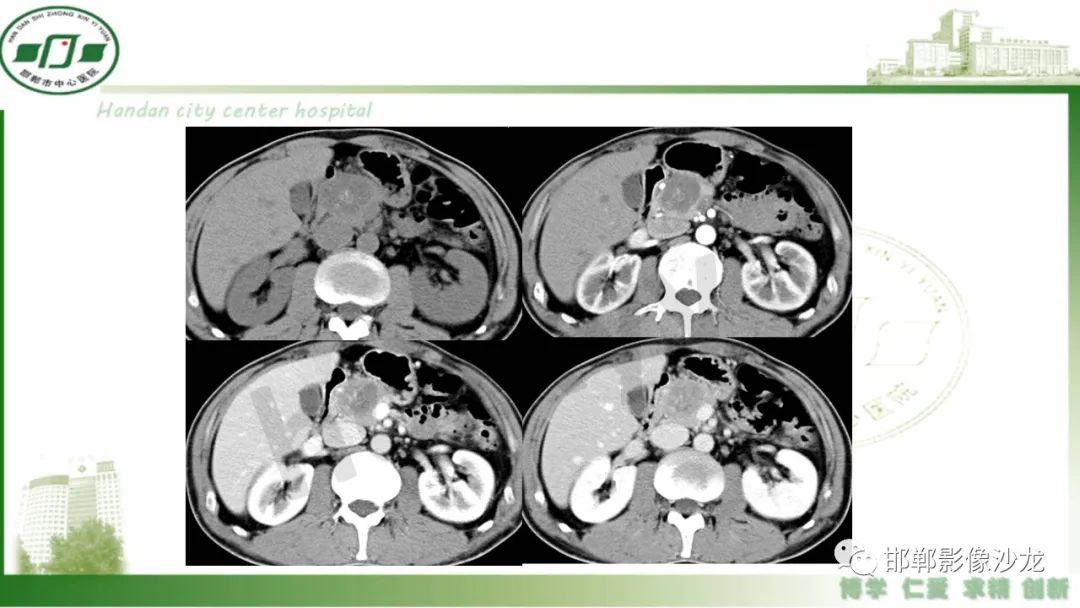

【PPT】肿块性胰腺炎

肿块性胰腺炎与胰腺癌的临床、实验室检查、影像学表现有时候很难鉴别,但两者的临床处理、预后又有很大的不同,因此我们平时工作中需要注意两者之间的区别,谨慎诊断,力争为患者及临床带来更大的帮助。